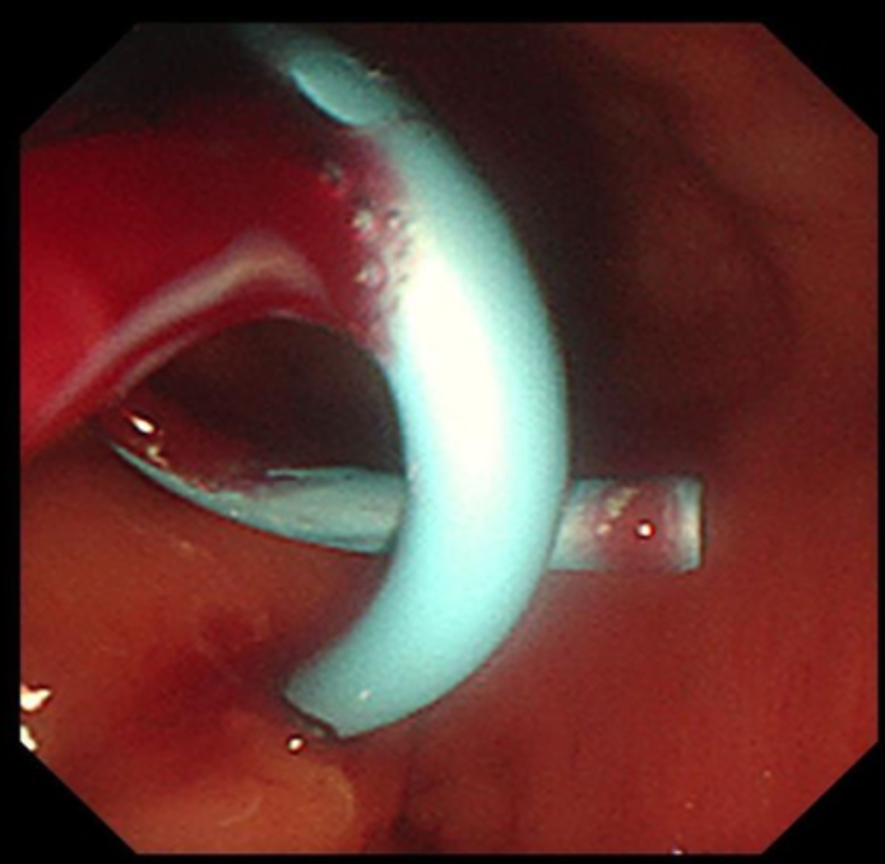

置入后的直肠内支架

经过充分的术前准备,消化内科刘华副主任医师在毛涛主任的指导下,和麻醉科、内镜室医护团队的密切配合下,凭借精湛的内镜技术,仅用时20分钟,便通过实时超声精准锁定病灶位置,巧妙避开血管、神经等重要解剖结构,合理规划穿刺路径并成功置入支架。手术全程经人体自然腔道操作,无体表切口,且未对直肠功能造成损伤。

术后4小时,大量脓液即经肛门顺利排出,患者发热症状消退;术后2天,尿频、尿急、肛门下坠等不适症状完全缓解;术后4天复查CT显示,盆腔脓肿已基本消退;术后5天,患者顺利康复出院。出院前,患者含泪对医护团队表达感谢:“医者仁心,你们不仅治好了我身体的病痛,更治愈了我心底的恐慌,感谢青大附院的医护人员们。”